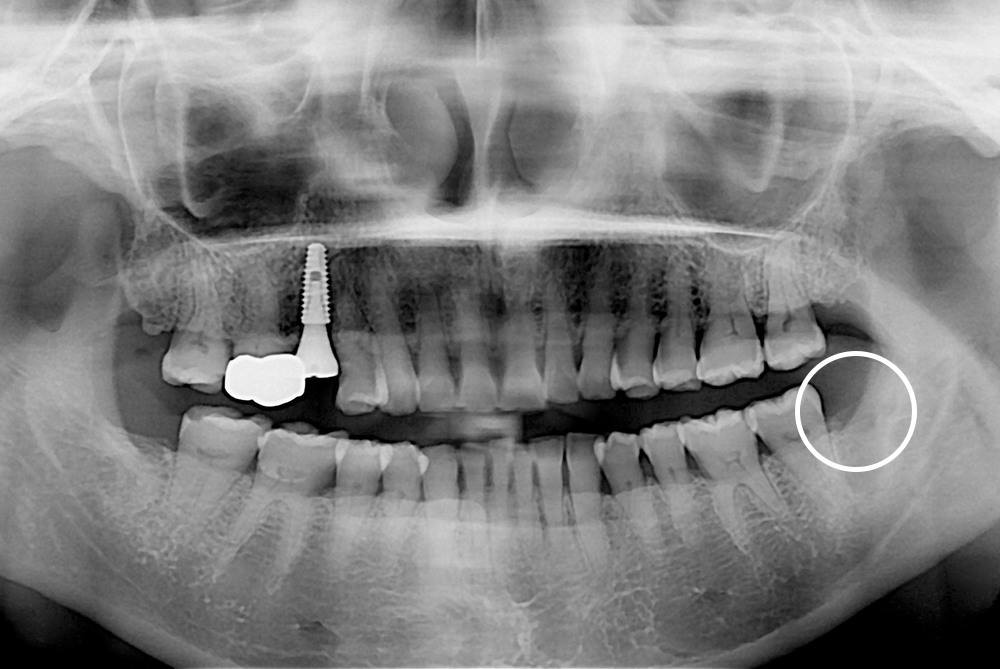

[사랑니] 매복 사랑니 발치

치료전 : 2020-05-19